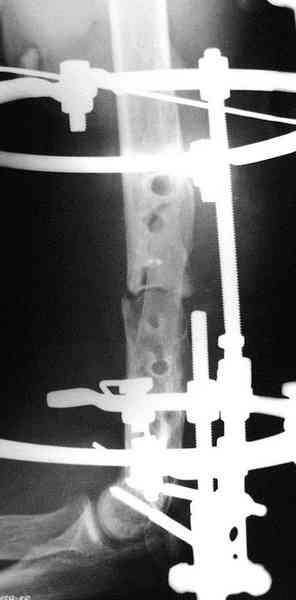

[Ortho] ложный сустав после остеосинтеза плеча

В подобном случае мы бы применили  чрескостный остеосинтез. Пример - в

приложении.